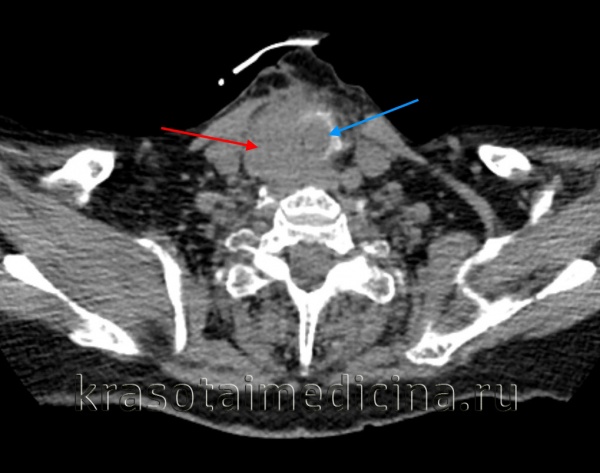

Обычно с имеющимися жалобами первично пациенты обращаются к эндокринологу. Врач направляет больных на консультацию к онкологу и отоларингологу. При выявлении признаков, характерных для фолликулярного рака щитовидной железы, дальнейшее обследование проводит онколог. План обследования включает в себя УЗИ, КТ и МРТ щитовидной железы. Перечисленные процедуры позволяют уточнить распространенность и структуру узла, а также наличие либо отсутствие четких границ новообразования.

Пациенту назначают анализы для определения уровня гормонов щитовидной железы. Осуществляют ларингоскопию для оценки степени вовлеченности гортани. Окончательный диагноз фолликулярного рака щитовидной железы устанавливают с учетом результатов гистологического исследования образца ткани, полученного при проведении тонкоигольной биопсии. Для обнаружения метастазов выполняют сцинтиграфию костей скелета, УЗИ и КТ печени, рентгенологическое исследование грудной клетки, МРТ головного мозга и прочие диагностические процедуры. Заболевание дифференцируют с другими формами рака и болезнями щитовидной железы неопухолевой природы.